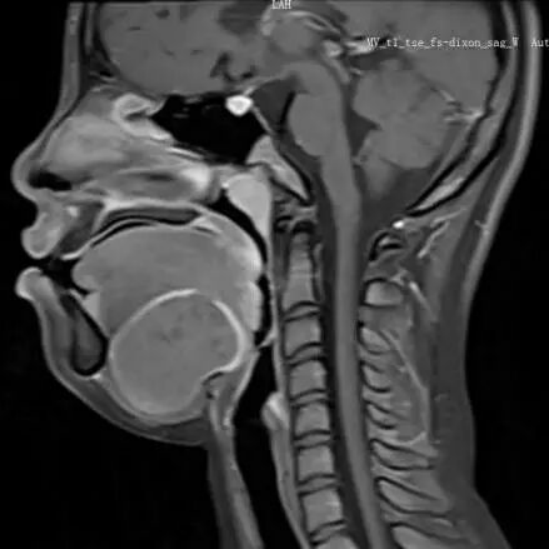

2026-03-06摔跤后下巴长出“鸭蛋”大包块,医生妙手“摘蛋”还其灿烂笑容

一名原本活泼开朗的初中女生,在短短两个月内性情大变,变得沉默寡言、逃避集体,放学后就将自己反锁在房间。这一切,都源于她下巴上悄悄“崛起”的一个鸭蛋大小的包块。近日,广州医科大学附属…